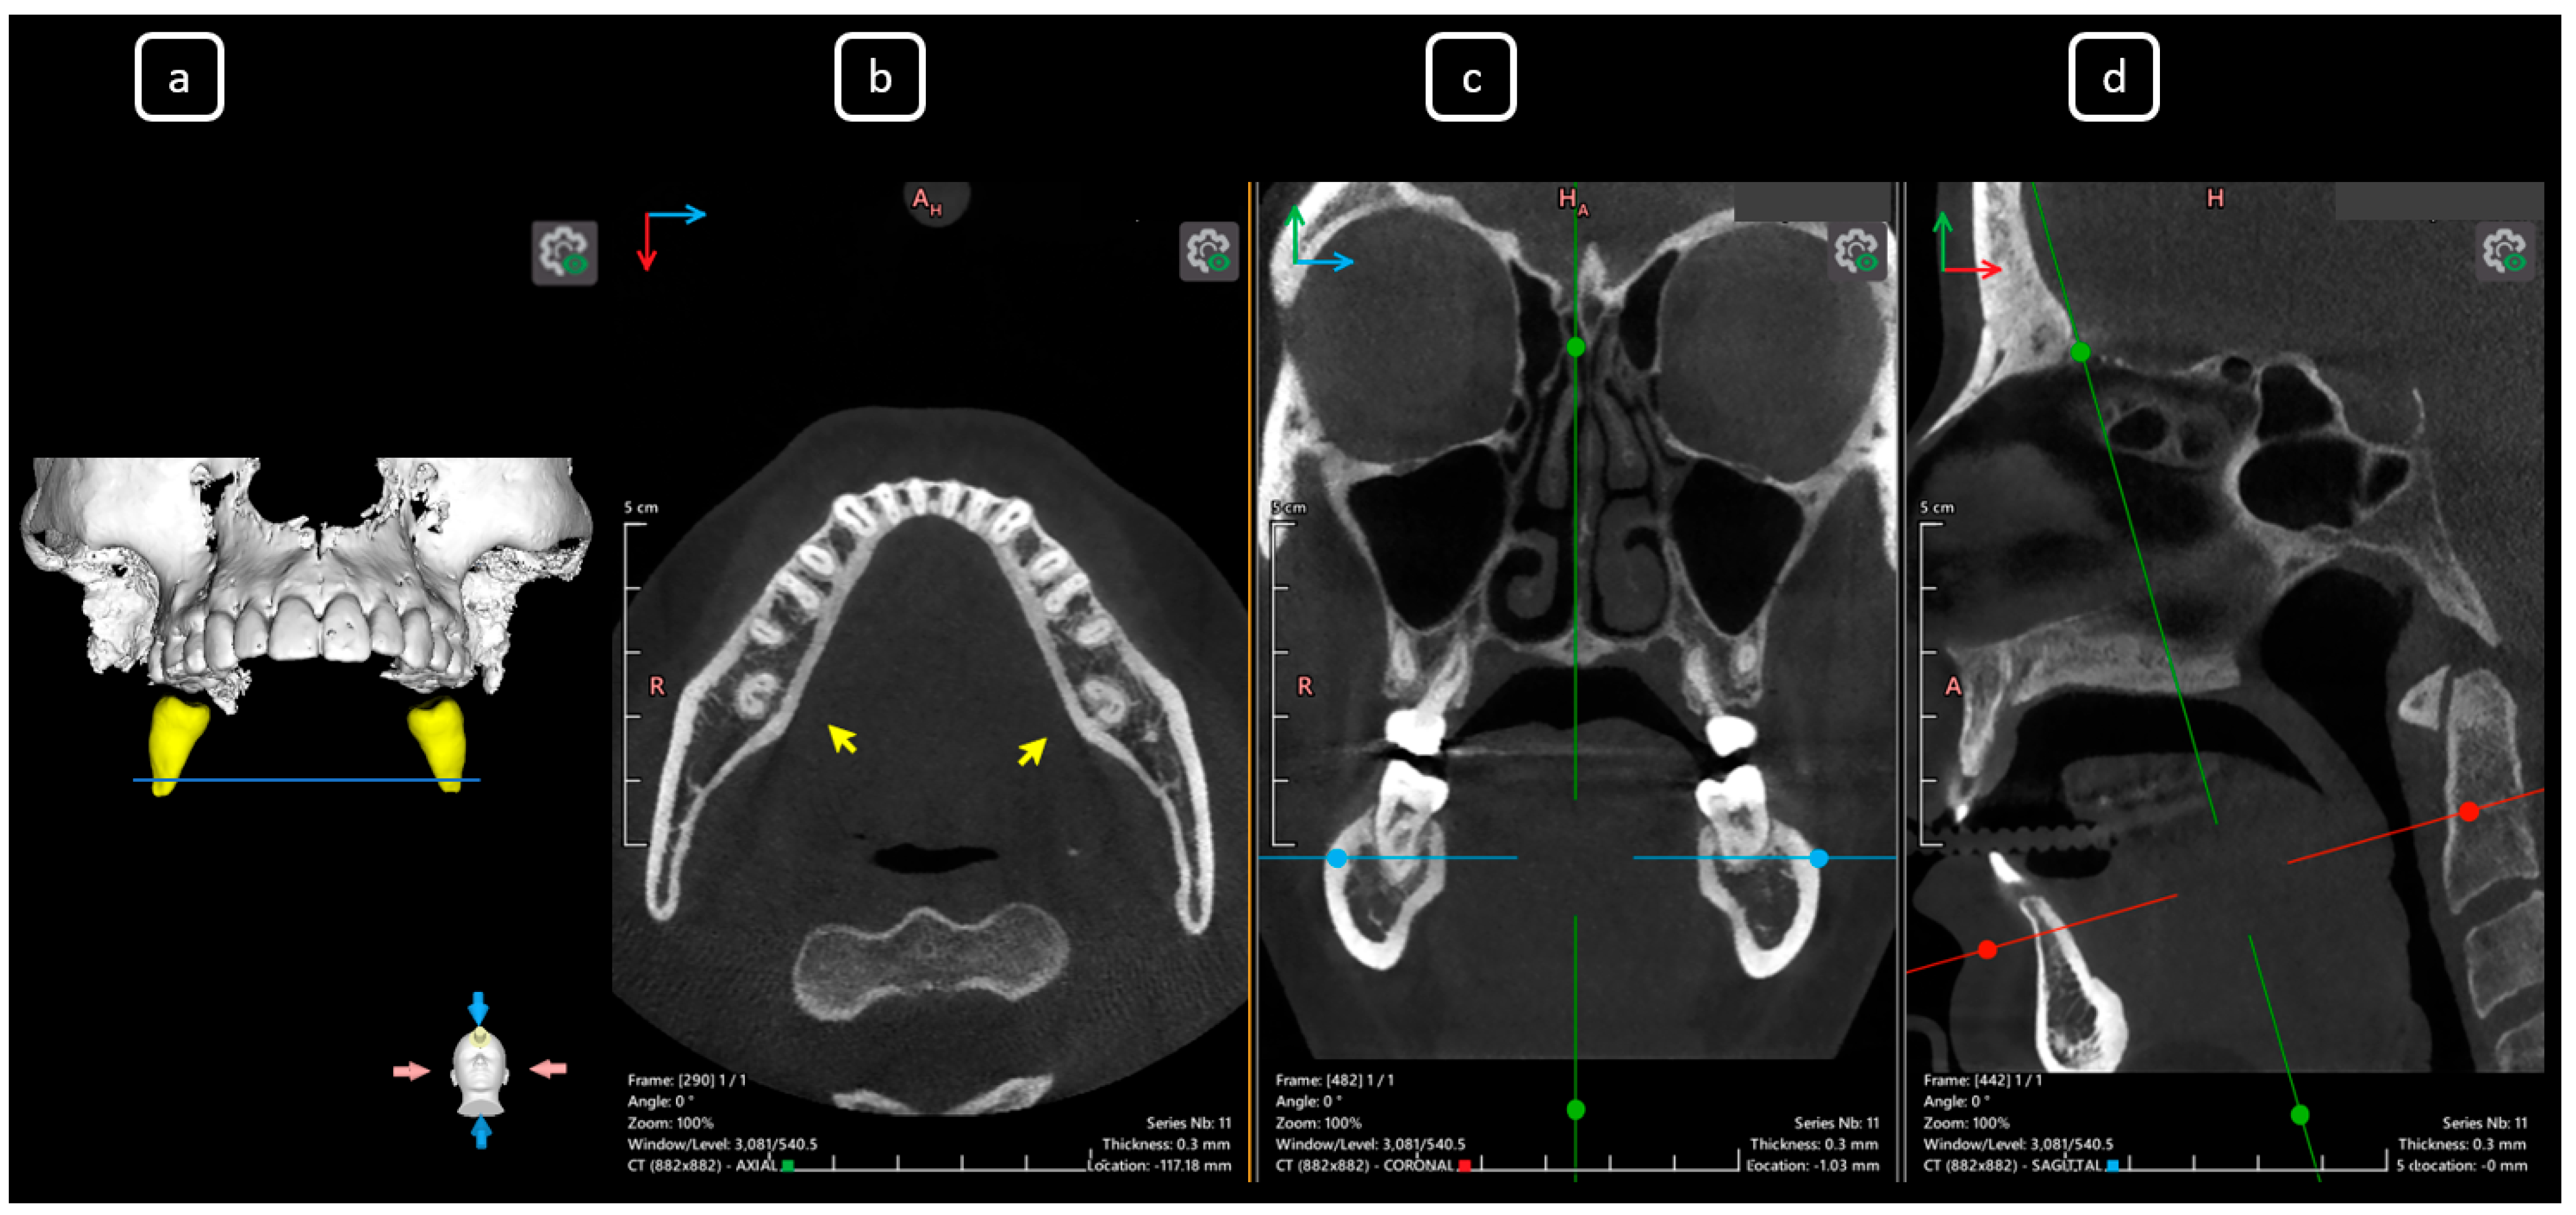

Imaging Findings of Clinical Significance in Endodontics During Cone Beam Computed Tomography Scanning of the Upper Airway—The Anterior, Bilateral, C-Shaped, Dual of Mandibular Root Canals: A Brief Case Report

García-Torres, E.; Guerrero-Falcón, D.L.G.; Bojórquez-Armenta, H.A.; Almeda-Ojeda, O.E.; Barajas-Pérez, V.H.; Solís-Martínez, L.J. Imaging Findings of Clinical Significance in Endodontics During Cone Beam Computed Tomography Scanning of the Upper Airway—The Anterior, Bilateral, C-Shaped, Dual of Mandibular Root Canals: A Brief Case Report. Diagnostics 2025, 15, 3157. https://doi.org/10.3390/diagnostics15243157